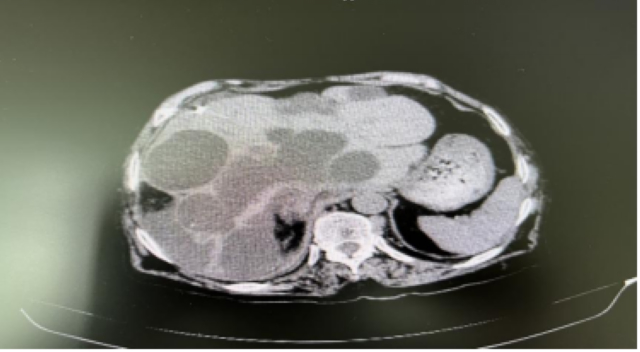

入住肝胆病科后,完善了CT等相关检查,考虑为肝多发囊肿,最大的囊肿约18.5cm×22.9cm×27.2cm。

鉴于魏婆婆除了巨块型肝囊肿,还有很多小的贯通型囊肿,加上年龄大,医生立即为其实施“肝囊肿置管引流术加囊肿固化术”,共引流出囊肿液3900ml,市面上常见的600ml的脉动得装上6瓶半。术后魏婆婆腹胀痛明显缓解。